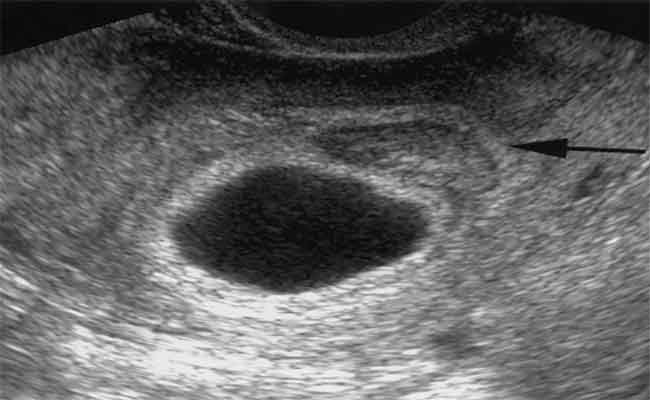

متى يظهر كيس الحمل في الرحم؟ وماذا لو كان فارغاً؟

ما هو كيس الحمل؟ واحدة من أولى علامات الحمل على الموجات فوق الصوتية هي ظهور كيس الحمل، الذي يحيط بالجنين…

byليلى اتسي30 يونيو 2022